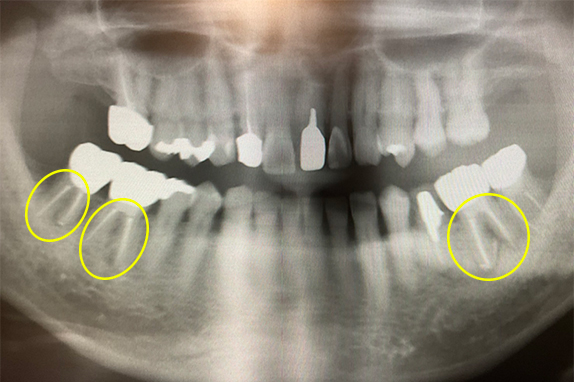

右の奥歯が痛くて噛めないという主訴で来院。7番をマイクロエンドで完全し6番にインプラントを埋入したケースです。

CASE 02 マイクロエンド(精密根管治療)+歯周基本治療

右も左も痛くて噛めないという主訴で来院。マイクロエンドをし歯周基本治療で改善したケースです。